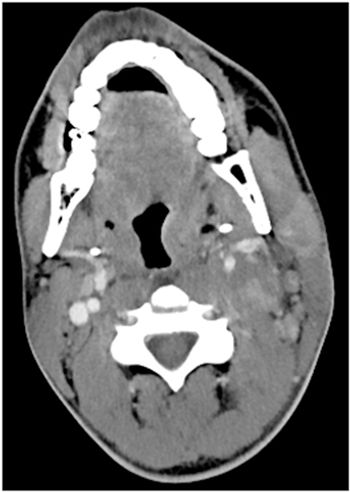

Image IQ: 20-year-old Male, Left Neck Pain

20-year-old male with no medical history presents with left-sided neck pain for 5 days.